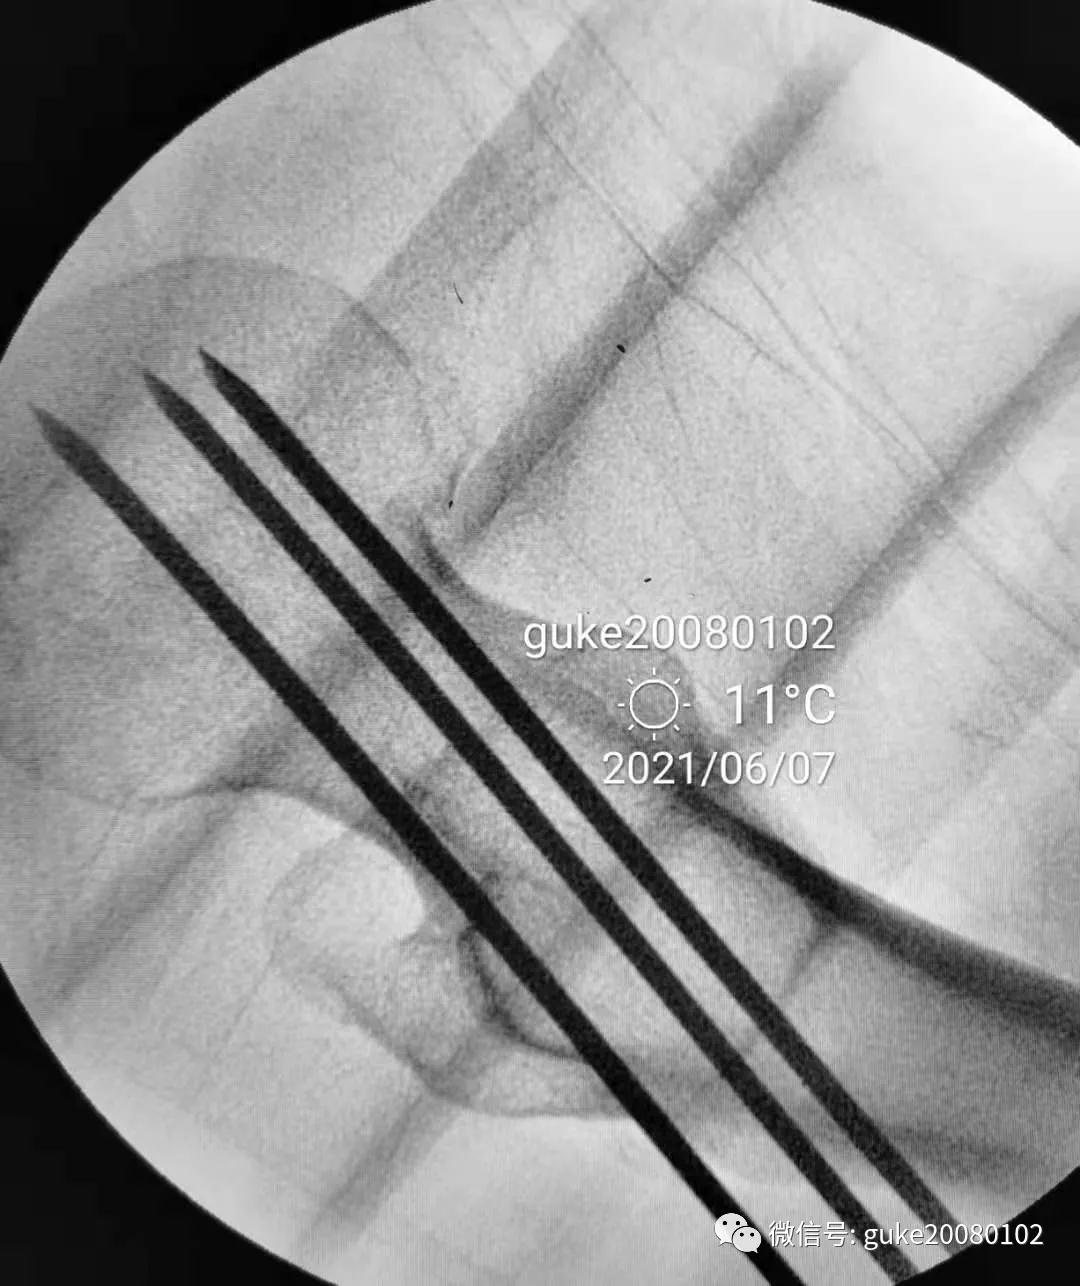

2.拧入三枚直径7.3mm空心钉,并逐步加压,稳定骨折断端。

最后透视: